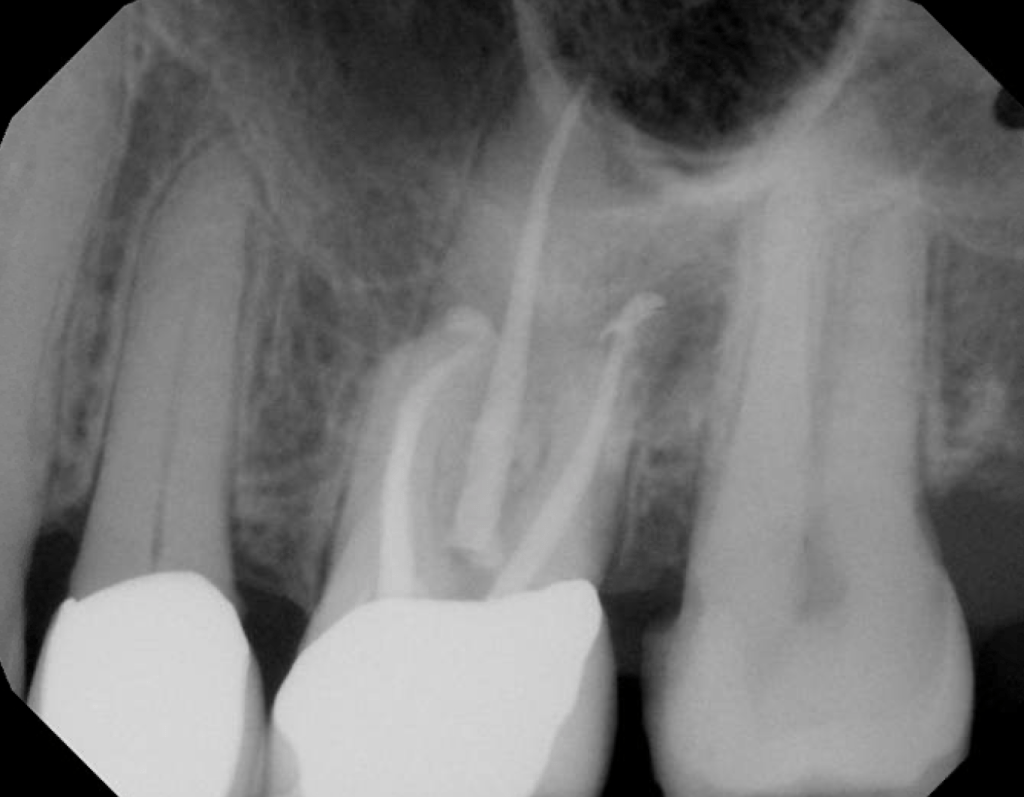

#19 NS-RCT

Dx: Previously Initiated with SAP

#9 S-RCT

Dx: Previously Treated with CAA